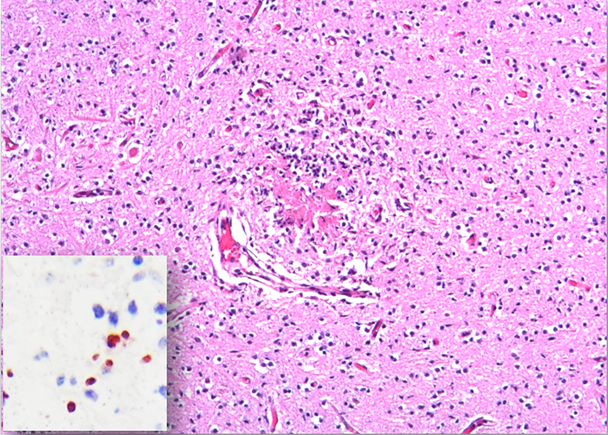

No significant gross lesions were observed in cases 2 to 5, and no microscopic lesions were observed in cases 2 to 3. However, in cases 4 and 5, histology revealed multifocal necrotizing non-suppurative encephalitis (Figure 2), lymphocytic and histiocytic myocarditis and myositis, and lymphocytic interstitial nephritis. Neospora caninum antigen was detected intralesionally in the brain of these two fetuses by IHC (Figure 2 inset) antibody titers to N. caninum ranged from 1/200 to 1/3200 in 10 of the 27 examined cows. Additionally, PCR for N. caninum DNA was positive in both cases. BVDV IHC was negative in liver, heart, and lung in cases 2, 4 and 5. Lastly, the IHC for Leptospira spp. was negative in kidney and liver from all fetuses. No antibody titers against Leptospira spp. were detected in any of the five fetuses. Other abortigenic pathogens were ruled out, such as Brucella spp. Their negativity was based on negative isolation of the pathogen and the absence of the pathogen in association with the compatible lesions.

The neuropil is disrupted by necrotizing non-suppurative multifocal encephalitis. Hematoxylin and eosin stain.

Inset. There is immunoreaction against Neospora caninum antigen within the affected sections of brain.

Figure 2 Fetal brain from case 4 aborted by Neospora caninum